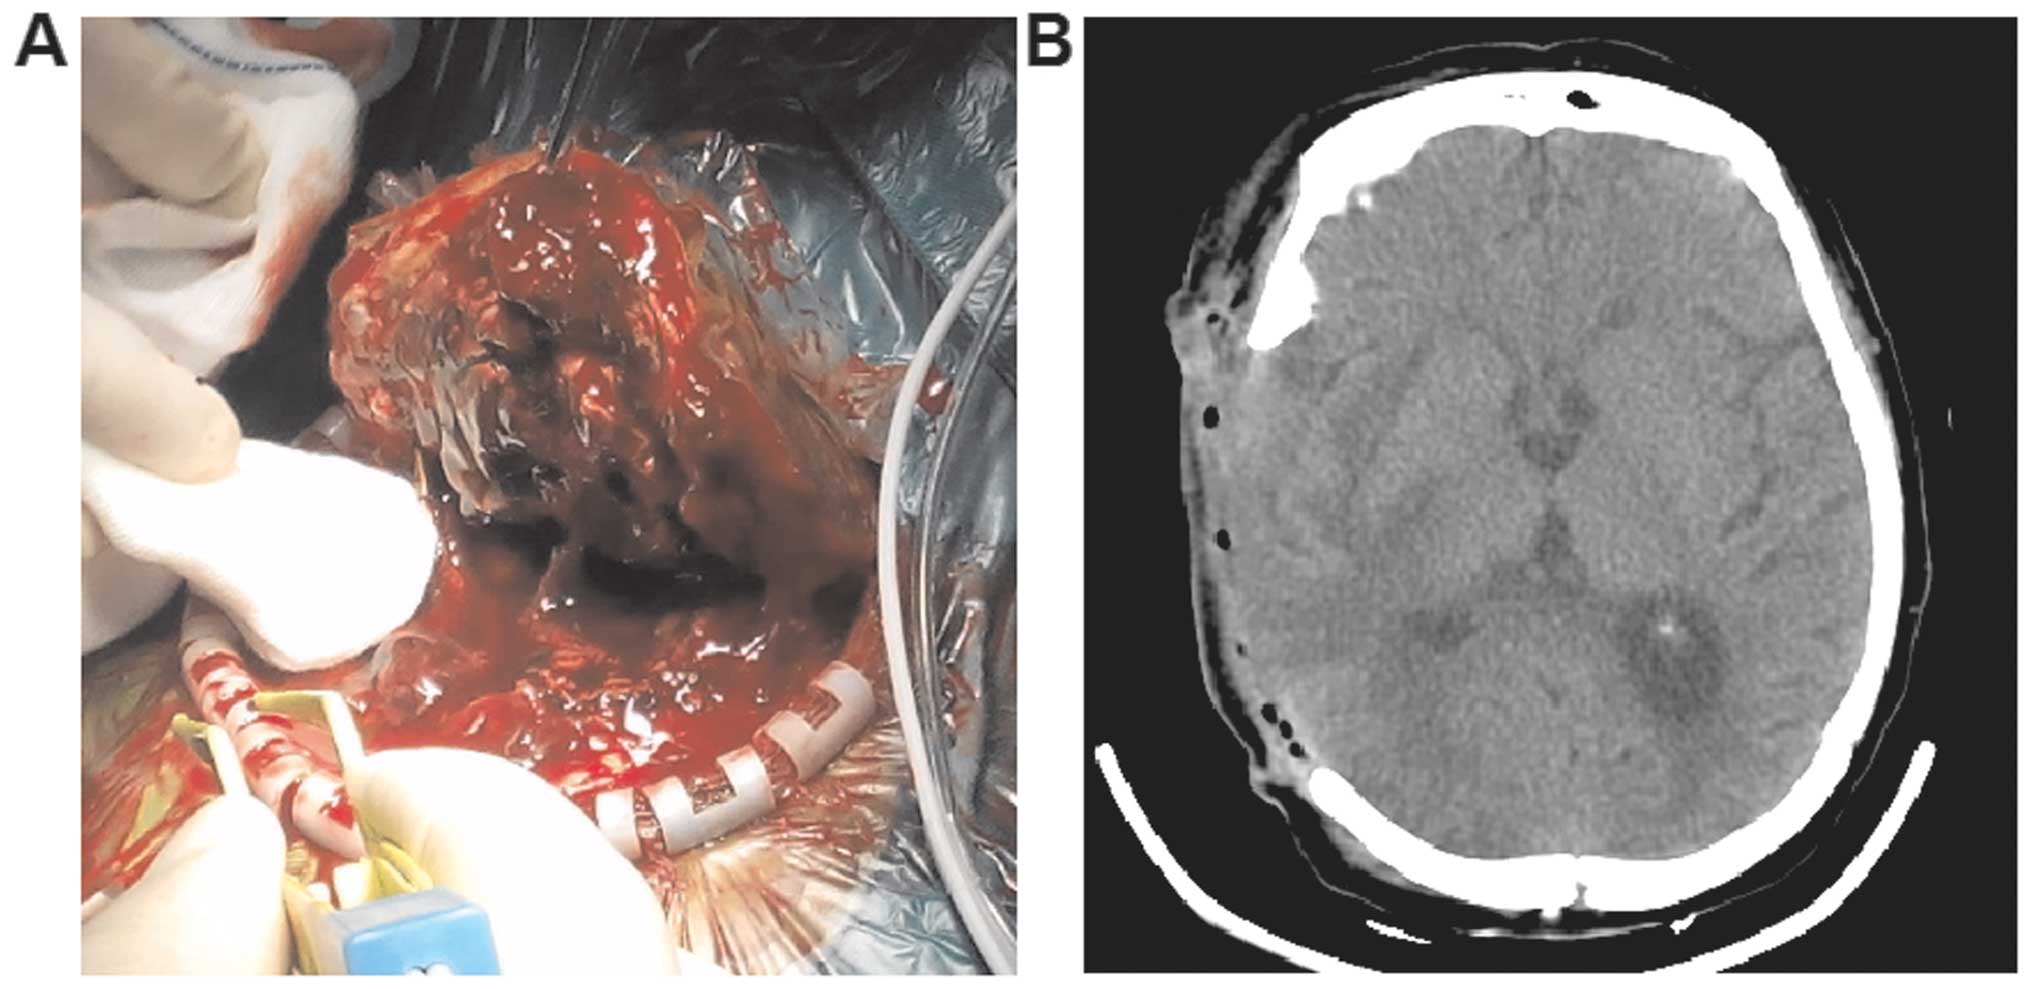

What is the procedure to remove a tumor?